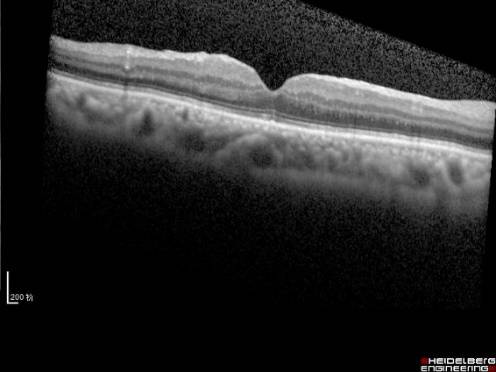

黄斑疾病多由先天发育异常或后天病损引起,临床上后者占绝大多数。一般来说,黄斑疾病多见于老年人,但目前黄斑疾病有低龄化和高发病的趋势。由于检查技术的日益精准,以往无法解释的视力问题越来越多的发现是由于黄斑部的细微病变造成的。常见的黄斑疾病包括年龄相关性黄斑变性(见图1)、特发性息肉状脉络膜血管病变、玻璃体黄斑牵拉综合征、黄斑前膜(见图2)、黄斑裂孔、高度近视黄斑病变(见图3)和中心性浆液性脉络膜视网膜病变等。

图2. 黄斑前膜

黄斑前膜

黄斑区的结构细微精细,其表面还有玻璃体后皮质和视网膜内界膜,有的时候,在后皮质和内界膜之间,会增殖产生一种特殊的病理性膜结构,叫黄斑前膜(见图10)。这层膜结构,与内界膜紧相连,同时也和玻璃体的后皮质紧密相连,当膜的增生,加上玻璃体的牵拉,使得黄斑被牵拉起来,于是产生视物的变形、视力下降。一旦产生了上述症状就需要及时通过玻璃体手术剥除增殖膜阻止视力的恶化,手术时间短,并发症少,大多数患者视力保持稳定,部分患者视力逐步提高。

图10. 黄斑前膜